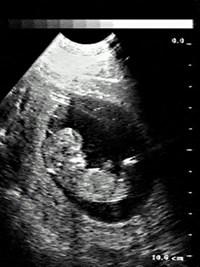

В настоящее время более распространен способ изображения эхо-сигнала по принципу «серой шкалы», когда наиболее сильные сигналы (от границ различных сред) изображаются белым цветом, а более слабые сигналы (от внутренних структур исследуемых сред) — различными оттенками серого цвета, вплоть до черного. Это изображение можно сохранить в виде видеокопии, сфотографировать, преобразовать для компьютерной обработки и произвести все необходимые измерения.

Преимущество метода состоит в том, что он позволяет определять структуру внутренних органов, не оказывая вредного воздействия на организм человека. В отличие от рентгенологических и радиоизотопных методов исследования ультразвуковое сканирование человеческого тела можно проводить сколь угодно часто безо всякого вреда для больного. В связи с этим ультразвуковое исследование получает все большее и большее распространение. Его безопасность превратила ультразвуковое исследование в рутинное даже при изучении зародыша у беременных женщин.